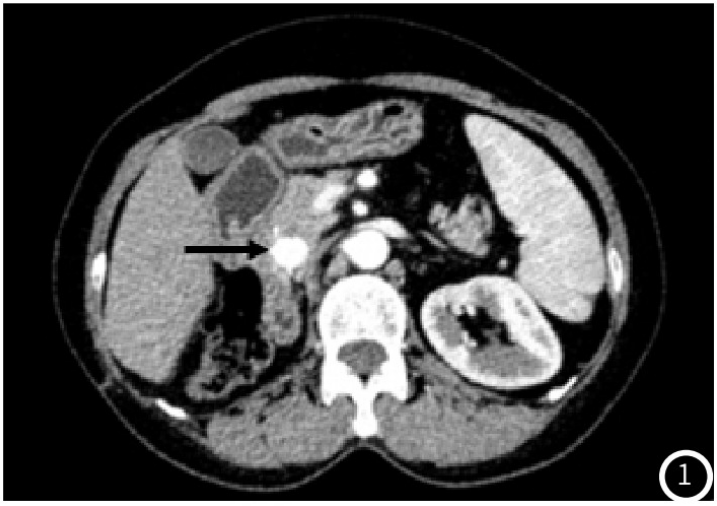

示胰头类圆形低密度结节,大小约14mm×12mm,增强扫描动脉期结节明显均匀强化(图1),强化程度高于正常胰腺实质,静脉期强化减低,边界清;术后4年常规胸腹部CT

图1 CT增强动脉期胰头部类圆形结节明显强化,边缘光整(黑箭头);